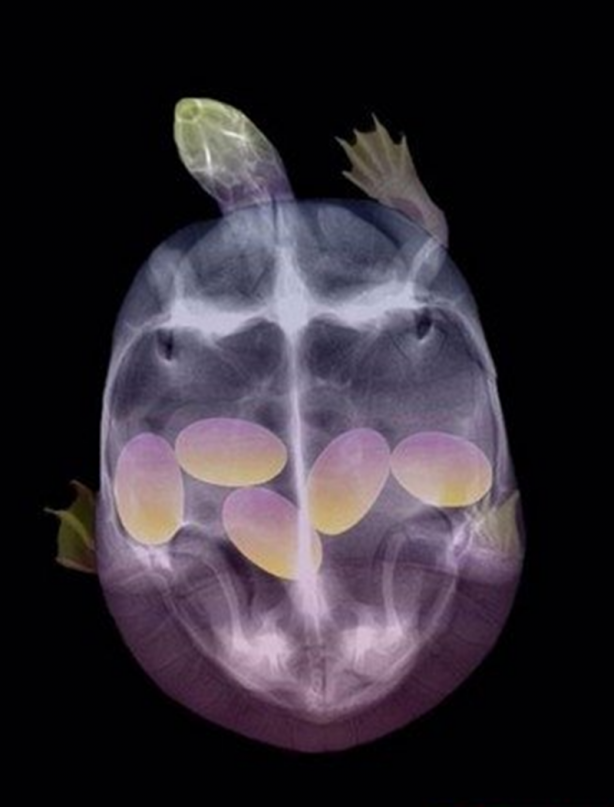

Hamile bir kaplumbağanın röntgen filmi.

Hamile kaplumbağa